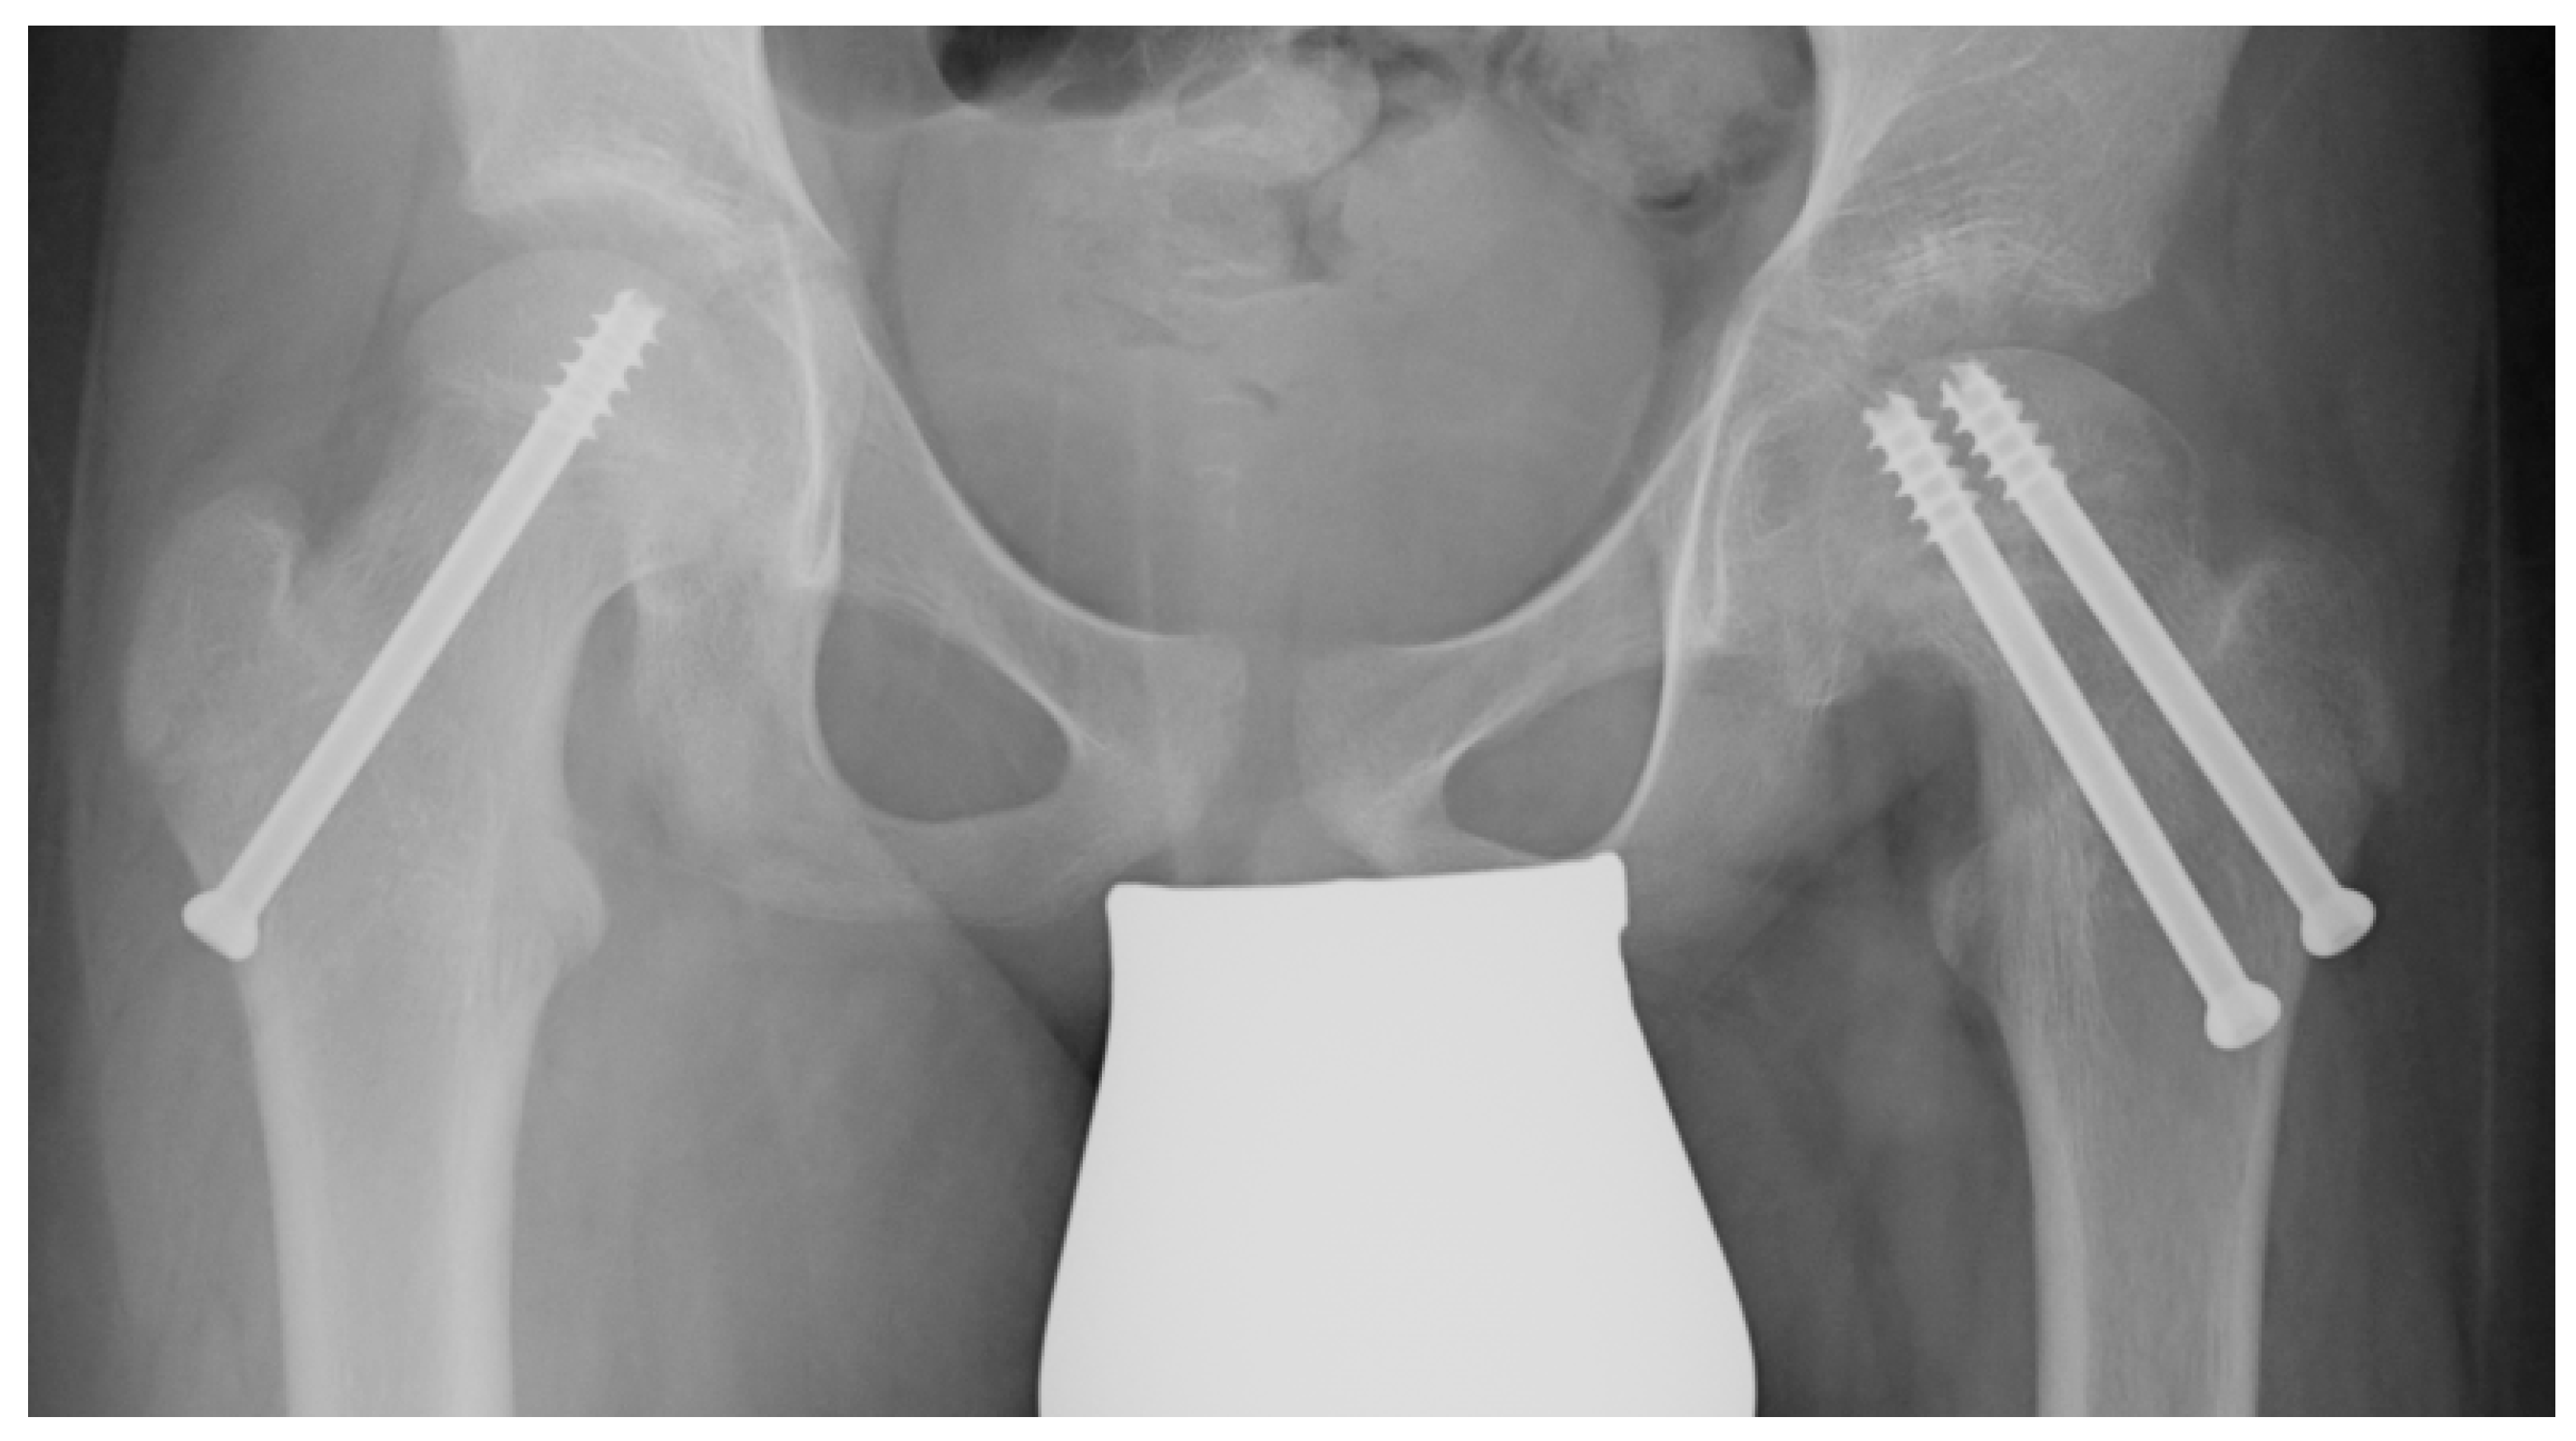

When the resection of the hinge is completed, the osteotomy is closed, reducing the head over the neck using a reducing maneuver. To check the correct alignment, a C-arm intensifier is used. Since the osteotomy slightly shortens the proximal femur, the reduction maneuver does not stretch the retinacular vessels. Making a lateral incision, under a fluoroscopic guide, two cannulated screws are used to fix the osteotomy. The joint capsule is carefully closed, and then the wounds are closed in layers. Prophylactic stabilization of the contralateral hip is usually performed using a single cannulated screw to reduce the risk of metachronous slippage (Figure 2) [23].

Figure 2.

A patient treated in the left hip using VASSCO and stabilized with two screws. On the right, a single cannulated screw is placed to reduce the risk of metachronous slippage.